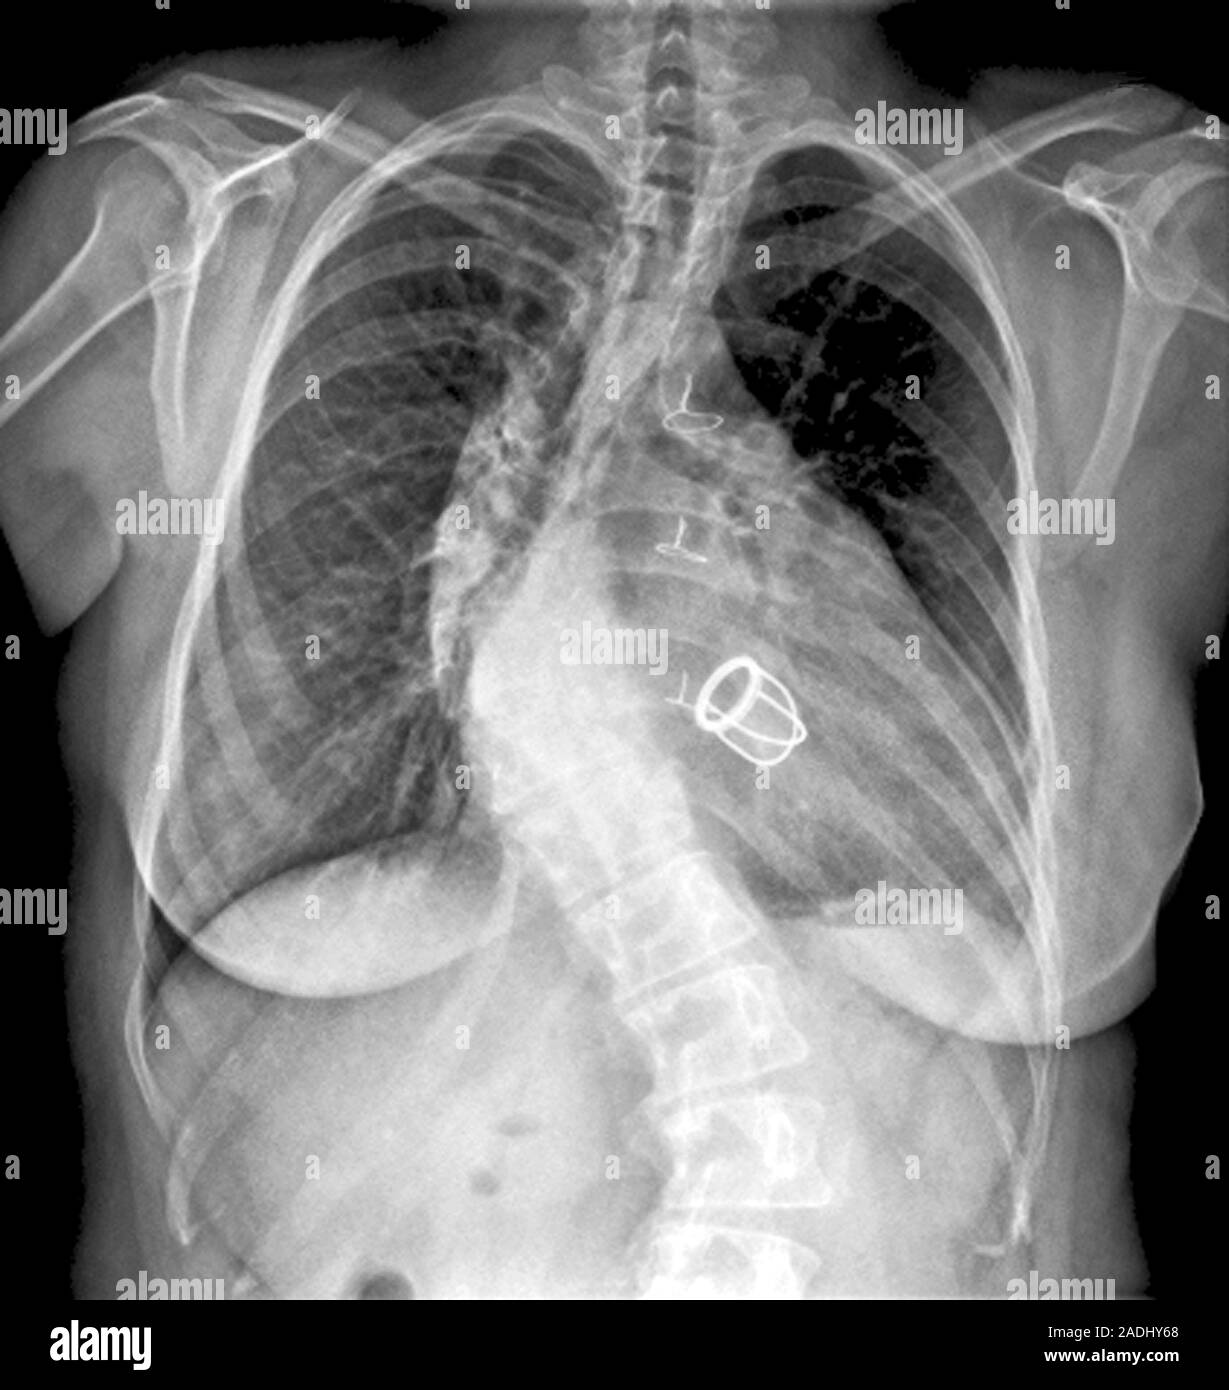

From www.alamy.com

Kyphoscoliosis. Frontal Xray image of the spine of a 35yearold woman Is Kyphoscoliosis A Disability Uk kyphoscoliosis is a combination of scoliosis and kyphosis, involving both sideways and forward curvature of the spine. Learn about the eligibility criteria. Learn about the signs, causes, and. I originally had a spondylolothesis, fused at 14. i am trying to get myself prepared for when i get the invite to apply for pip. scoliosis is not a. Is Kyphoscoliosis A Disability Uk.

Xray (front view) of the torso of an 82 year old female patient Is Kyphoscoliosis A Disability Uk keds is a rare type of eds with muscle hypotonia, kyphoscoliosis and joint hypermobility. Learn about the signs, causes, and. kyphoscoliotic eds is a genetic condition that affects the collagen in the connective tissues, causing joint hypermobility, skin fragility,. I originally had a spondylolothesis, fused at 14. scoliosis is not a disability in the uk unless it. Is Kyphoscoliosis A Disability Uk.